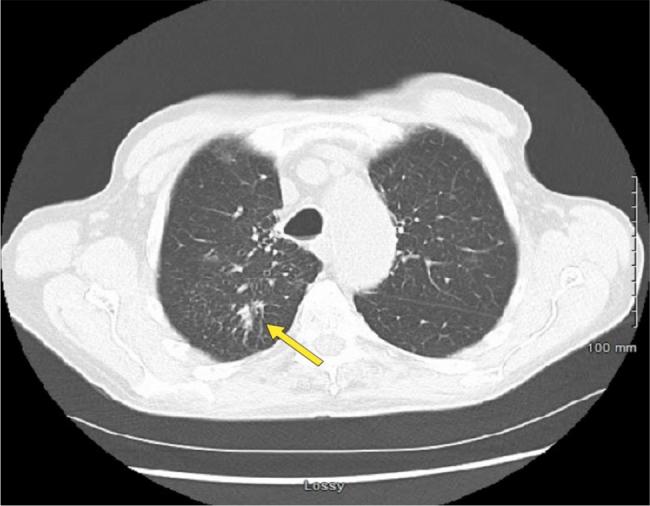

We present a case of a 78-year-old male with CLL receiving chemotherapy, who developed burning pain in the tongue and oral mucosa, accompanied by a non-productive cough. He was initially diagnosed with pneumonia, but further investigation revealed co-infection involving and .

The coexistence of and underscores the complexity of infectious complications in CLL. The patient's chemotherapy was halted due to active pneumonitis observed on imaging in order to improve his leukocyte count. Antifungal therapy was not initiated due to a lack of evidence of invasive fungal infection. Antimycobacterial therapy for complex was initiated.

我们报告一例78岁接受化疗的CLL男性患者,他出现舌部和口腔黏膜灼痛,并伴有干咳。他最初被诊断为肺炎,但进一步检查发现同时感染了两种病原体。

两种病原体的共存强调了CLL感染并发症的复杂性。由于影像学检查发现活动性肺炎,为了提高白细胞计数,患者的化疗被暂停。由于缺乏侵袭性真菌感染的证据,未开始抗真菌治疗。开始了针对复杂分枝杆菌感染的抗分枝杆菌治疗。